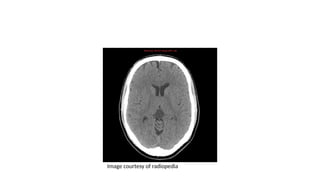

PINEAL CYST

• They are common, usually asymptomatic, and typically found

incidentally.

• Common in women.

• The cyst typically contains proteinaceous fluid that, as a result, does

not follow CSF on imaging.

• Internal haemorrhage may also be present

CT Findings

• Pineal cysts appear as well circumscribed fluid density lesions.

• A thin rim calcification is seen in ~25%.

• Thin, smooth peripheral enhancement is also often seen.

• The internal cerebral veins are elevated and splayed by the cyst.

Image courtesy of radiopedia

Image courtesy of Radiopedia rID: 2321

Image courtesy of radiopedia rID:

2646

• #42 CT of the brain demonstrates no focal mass or abnormality. Incidental note is made of a 20 mm pineal cyst.

• #43 Incidentally well-circumscribed fluid density lesion with rim calcification is seen at pineal topography with no contrast enhancement.